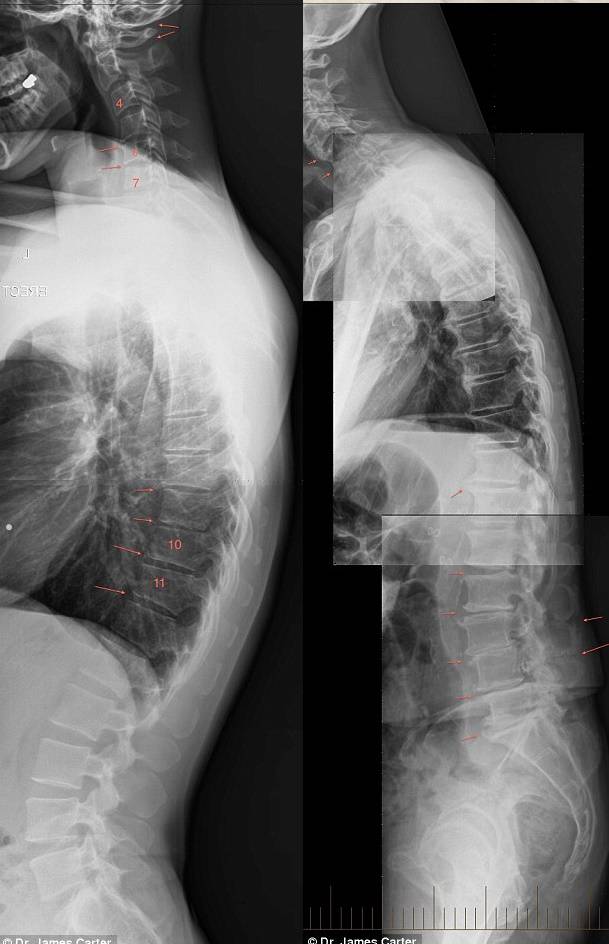

Il dottor James Carter, un famoso chiropratico australiano, di Niagara Park nella Nsw Central Coast, ha pubblicato sul Daily Mail Australia le lastre di alcuni bambini di 7 anni nelle quali si vedono i danni causati dall’uso eccessivo di Smartphone e Tablet alla loro spina dorsale.

Tale condizione chiamata “text neck” (letteralmente collo da testo) è, purtroppo, comune a molti bambini e adolescenti, come testimonia il dottor Carter il quale dichiara di aver visto un notevole aumento di questi disturbi negli ultimi anni. «Ho iniziato a vedere molti casi di questo tipo negli ultimi due anni, specialmente in bambini e adolescenti che trascorrono troppe ore con la testa china a scrivere sms. Tali ragazzi sembrano avere una schiena a ‘zainetto’, che spesso fa male o provoca dolore a testa, collo e spalle nonché intorpidimento e dolore a mano e braccia e, addirittura, ansia».

Da quanto sostenuto dallo specialista sembra che il 50% delle persone affette da tale disturbo, il Test Neck, sono adolescenti in età scolare. I ragazzi, così come dimostrano le radiografie, si ritrovano con la schiena curva e seri problemi di postura.

Ecco quindi spiegate le foto shock che dimostrano quanto sostenuto dal dottor James Carter e avvalorato anche da un altro dottore, Kenneth Hansraj, il quale spiega che il peso sul collo aumenta quando la testa si curva in giù, postura utilizzata quando si utilizzano Smartphone e Tablet.